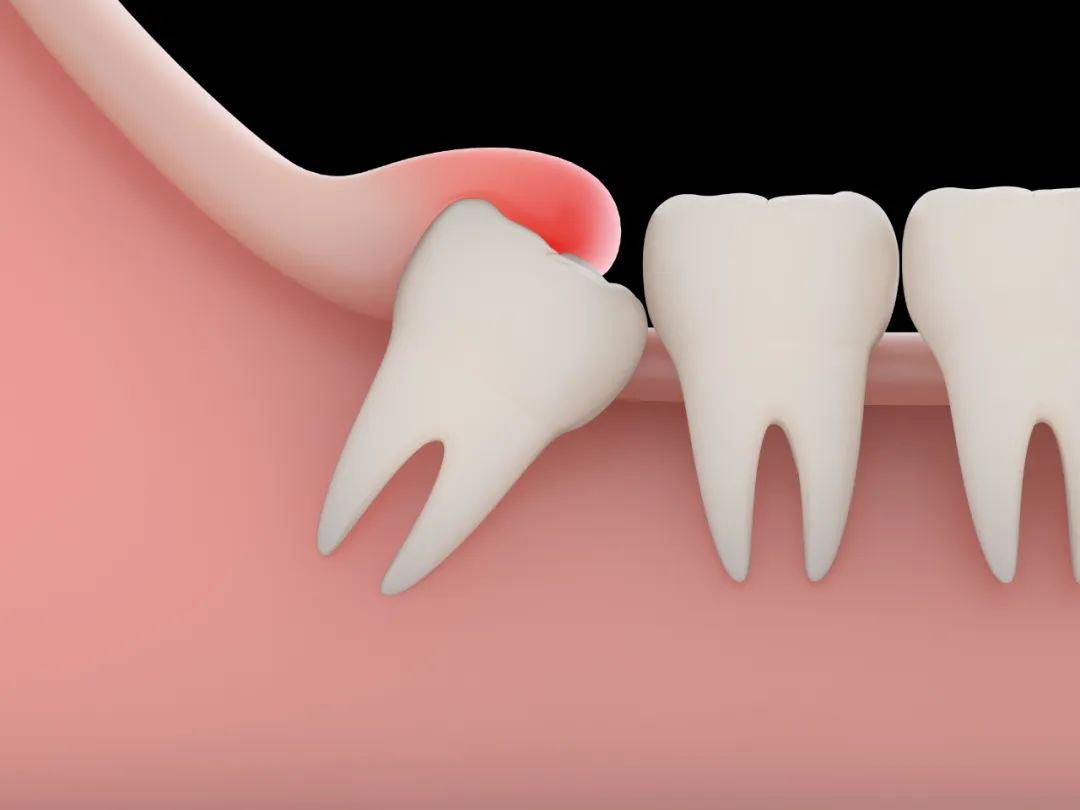

不管痛不痛,长歪的智齿都要拔!也就是说,尽管暂时没有引起疼痛,那些长歪的智齿,越早拔除越好。发炎的智齿是身体上的一个病灶,会产生很多炎症因子和毒素等有害物质。

牙齿肿痛很严重,说明局部感染很严重,虽说不是立即拔牙的好时机,但也应该去医院找医生开药、冲洗,实在不行,咨询药师和医生,服用一些常用的抗生素。

等智齿没那么痛了,牙龈周围的红肿也消失了,就是去找医生拔牙的好时机!长痛不如短痛,更何况,打了麻药,拔牙其实也没那么痛。